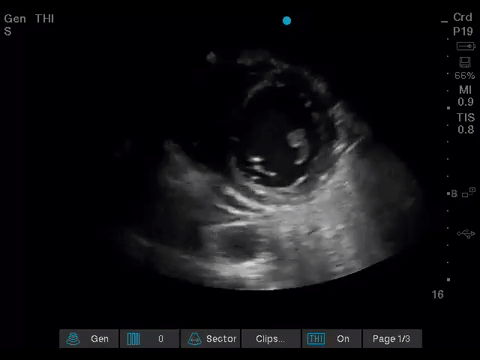

Before giving their clinical interpretation of the LUS findings, the POCUS team also scanned the heart and vasculature to obtain a more complete picture.

A comprehensive echocardiogram confirmed the POCUS findings. Her depressed LVEF was thought to be due to either septic cardiomyopathy or chemotherapy toxicity.